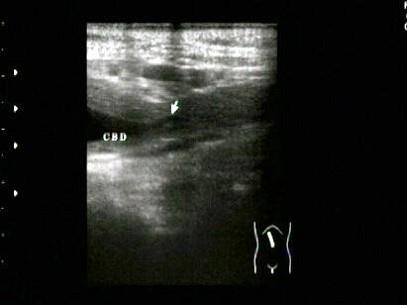

胆总管出现图中所示特点,称为?(?)A.双筒枪征B.海鸥征C.鸟嘴征D.鼠尾征E.平行管征

问题 胆总管出现图中所示特点,称为?(?)

选项 A.双筒枪征 B.海鸥征 C.鸟嘴征 D.鼠尾征 E.平行管征

答案 D